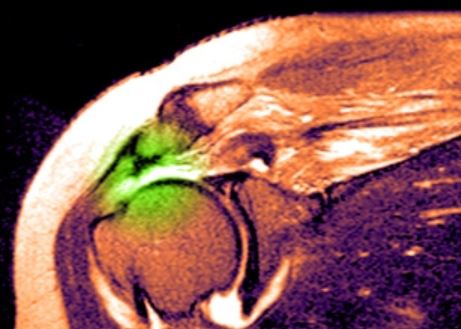

МРТ плечевого сустава. Т2-взвешенная корональная МРТ. Разрыв вращательной манжеты. Цветовая обработка изображения.

image

При МРТ плечевого сустава высоким сигналом на Т2-взвешенных изображениях от поверхности сустава до субакромиальной сумки можно косвенно указать на разрыв вращательной манжеты. Частичные разрывы чаще всего наблюдаются на передней поверхности сухожилия m. supraspinatus, реже — у большой бугристости или сухожилия m. infraspinatus.

МРТ плечевого сустава может показать субакромиальное скопление жидкости, что также является косвенным признаком разрыва вращательной манжеты. Частичный разрыв может быть виден на Т1-взвешенной корональной МРТ, а передний разрыв — на Т2-взвешенной.